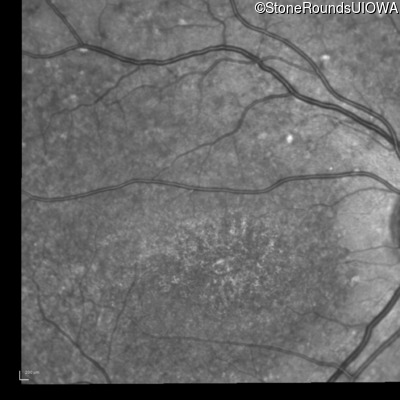

Blue Autofluorescence - Right - 10/125 -2 sc

Exemplar